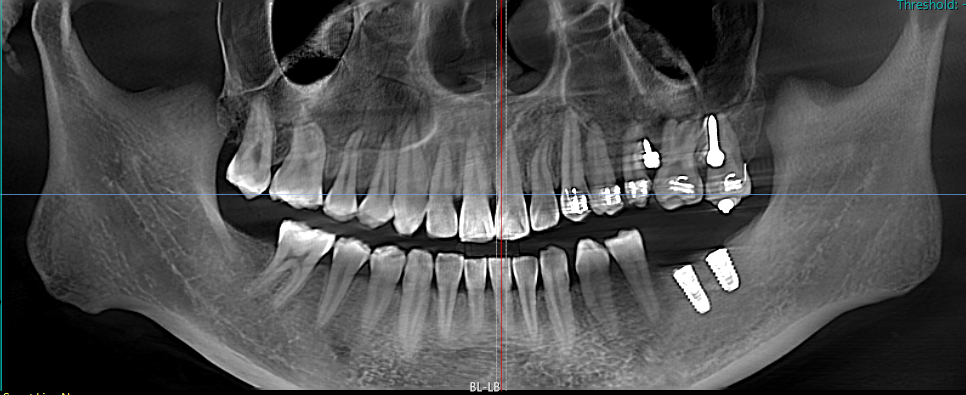

小王右下两颗大牙缺失了两年多,她一直没太在意,直到吃东西越来越费劲,才引起重视来到区中医医院口腔科就诊。易建飞通过CBCT影像检查发现,小王缺失牙齿对应的上颌牙竟然像"疯长的野草"一样伸长了2.3mm!这种情况如果直接种牙,不仅效果不好,还可能导致咬合创伤。

面对此情况,易建飞团队决定采用"正畸-种植联合疗法",先正畸后种植,先改善牙齿排列和咬合关系,为种植牙提供更理想的条件,也为种植牙齿提升美观性、功能性和长期稳定性。这种综合治疗方式能够更好地满足患者的需求,实现更自然、协调的口腔修复效果。

易建飞提醒,后牙缺失超过3个月就需要及时干预,否则可能导致邻牙移位、咬合紊乱等问题。60%的种植失败案例都源于咬合空间不足,而"先正畸后种植"的联合疗法可以有效避免这些问题,甚至减少30%的骨增量需求。